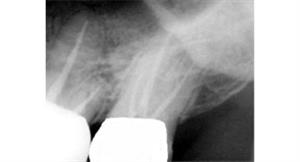

Root Canal Treatment

Before

After

A root canal procedure (endodontic treatment) is often required to save an infected tooth. Bacteria can enter a tooth through a cavity or a damaged filling. When this happens, the tooth can become abscessed, meaning the pulp inside the tooth becomes infected. An abscessed tooth can be quite painful and cause swelling in the surrounding gum tissues. If left untreated, it can cause several oral health problems. A root canal procedure removes the infected pulp and any other infected tissues within the tooth.